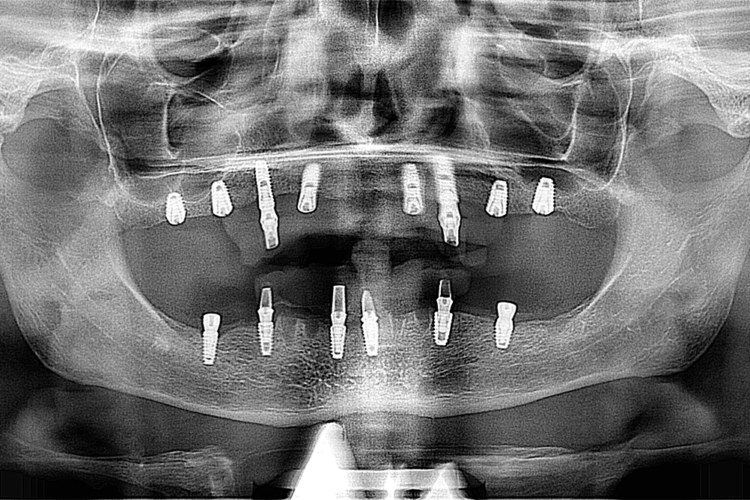

Caz reabilitare implanto-protetica

Pacient in varsta de 68 ani, s-a prezentat in clinica noastra cu cerinta stricta de a avea o lucrare fixa desi era edentat subtotal,  iar dintii restanti aveau indicatie de extractie. I s-a propus ca plan de tratament o protezare fixa pe implanturi. Planul de tratament a inclus 8 implanturi la maxilar si 6 la mandibula care vor fi finalizate prin lucrari protetice insurubate din zirconiu. Pana la finalizarea lucrarilor definitive, pentru realizarea unor lucrari echilibrate ocluzal i s-a propus si realizat temporizare prin lucrari de PMMA.